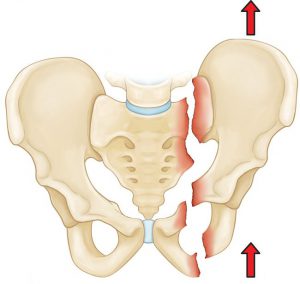

Hip fracture surgery is one of the treatment options available for those who have experienced a hip fracture. This procedure can be somewhat challenging, as it sometimes involves making an incision in the skin around the hip area to realign the broken bones. Despite the seriousness of a fracture in the hip area, recovery can take approximately four to six months. The treating orthopedic surgeon will determine the activities the patient should perform during this period.

To treat a hip fracture, traditional or surgical methods can be used. Before the treating doctor decides on the possibility of performing hip fracture surgery, a comprehensive diagnosis is required, including clinical examination and X-rays or magnetic resonance imaging (MRI).

The goal of hip fracture surgery is to treat the fractured joint or bone using one of two methods:

- Performing an open incision (surgical wound) in the affected area to realign the broken bones if they have shifted from their original position due to the injury.

- Hip fracture can also be treated without surgical incision, but this procedure is only suitable when the bones have not shifted significantly from their original position.